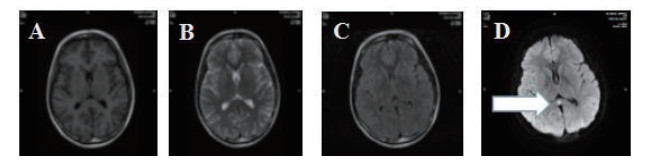

磁共振提示胼胝体局灶病变多为轻症患者(图 3);磁共振提示胼胝体双侧放射冠部散在病变多为中型患者(图 4);磁共振提示胼胝体双侧放射冠区弥漫性病变多为重症患者(图 5,6)。

| 图 3 ABCD为同例患者,病变为胼胝体局灶病变(箭头所示);EFGH为同例患者,病变为胼胝体右侧放射冠区局灶病变(箭头所示) |